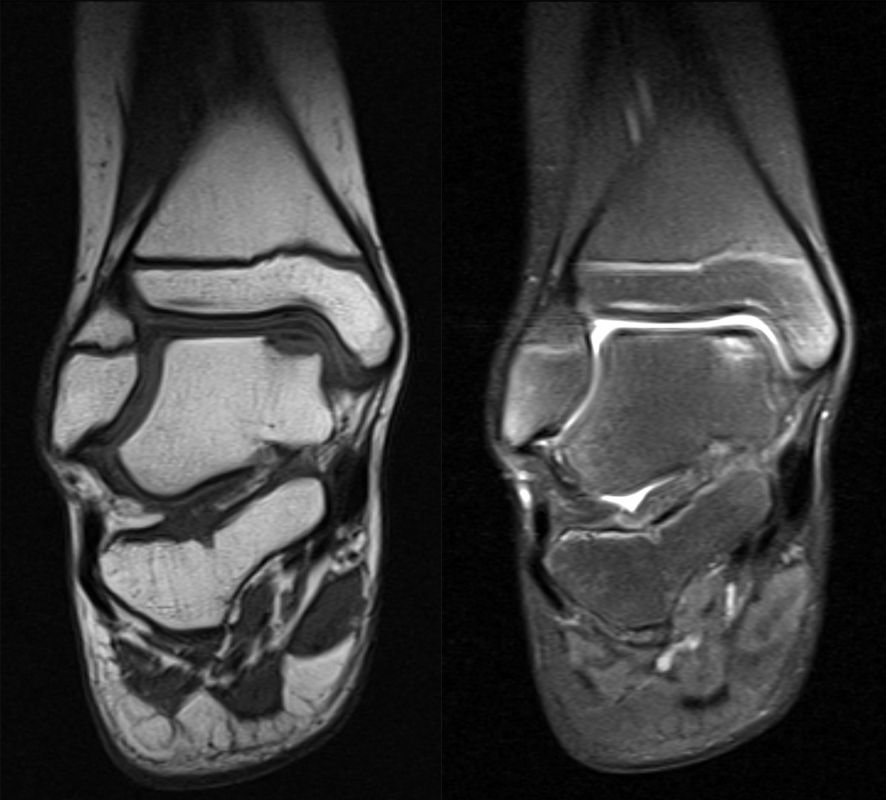

MRT

Die Kernspintomographie hat ihre Stärke in der Darstellung von Weichteilverletzungen. Insbesondere Verletzungen der Wachstumsfuge, des Periosts und der Bänder lassen sich gut visualisieren. Nachteilig ist die Untersuchungsdauer von 20-30 Minuten. Bleibt das Kind während dieser Zeit nicht ruhig liegen, kommt es zu Bewegungsartefakten, welche die Beurteilbarkeit der Bilder beeinträchtigen.